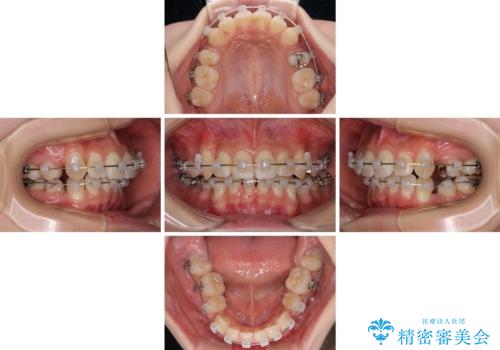

前歯の歯並びを治したい ワイヤー装置での抜歯矯正

- 前歯の叢生と八重歯を気にして来院された患者様です。

叢生が強く、奥歯の咬合も左右差が大きかったため、上下左右4本を抜歯して、ワイヤー矯正を行うこととしました。

20歳前後と年齢が若かったため、非常にスムーズに歯列が整い、1年半をかけずに治療を終えることができました。